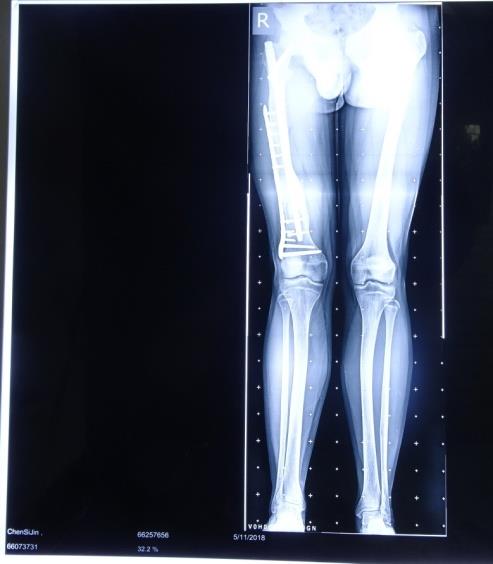

十堰市XX医院2018年5月11日X线片(片号:×××)示:右股骨钢板内固定术后,股骨干增粗,骨质密度不均。

右股骨钢板内固定术后